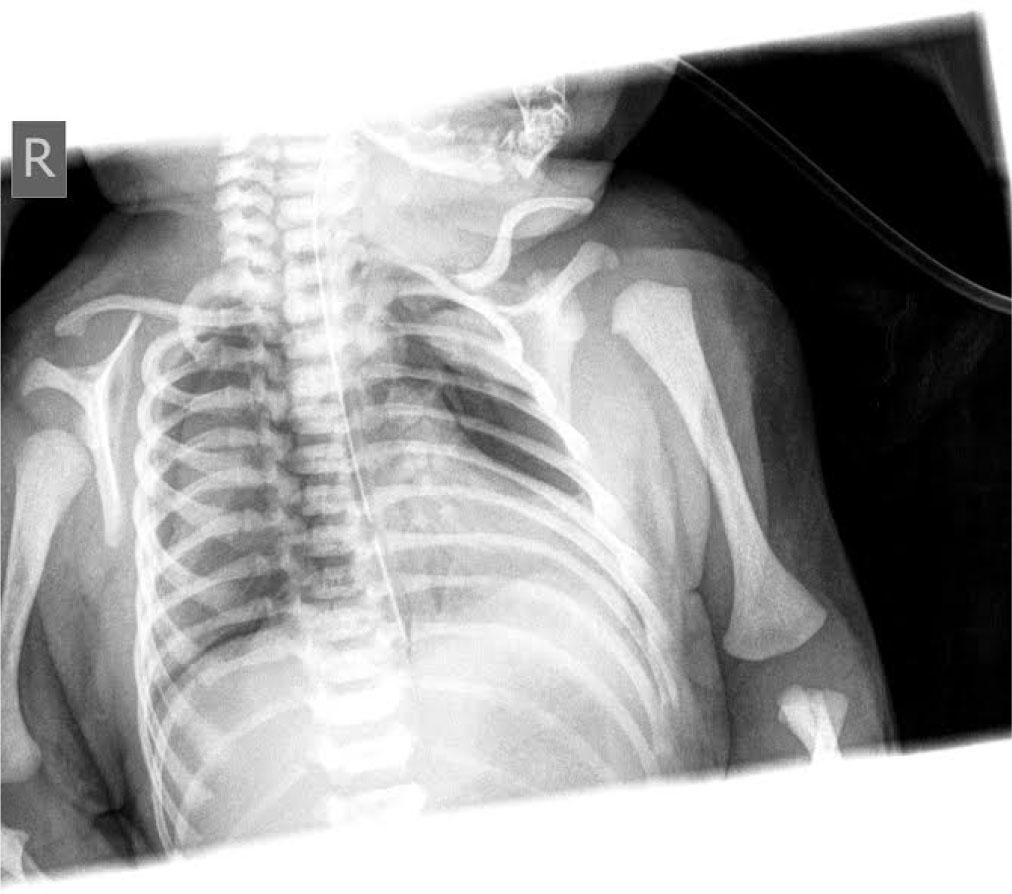

A chest radiograph revealed bilateral partial pneumothorax

A term male infant, weighing 2700 grams at birth, was born at 39 weeks to a healthy mother (blood type O, Rh positive) delivered spontaneously by vaginal route. Pregnancy was well monitored and unremarkable. The infant cried immediately after birth and did not require any interventions. He had a birth weight of 2700 grams, a length of 52 cm and a head circumference of 34 cm. Apgar scores were 9 and 9 at 1th and 5th minutes, and infant was transferred to the postnatal unit with his mother for regular postnatal care. During the third hour of age, his skin started to become diffusely livid with evidence of respiratory distress, tachypnea (respiratory rate = 63/min) and heart rate 136/min. He was transferred to the neonatal intensive care unit (NICU) for investigation and further management. On admission, his vital signs showed a temperature of 36.6 °C, heart rate of 101 per minute and respiratory rate of 68 per minute. His blood pressure was 77/50 mmHg and his weight reduced to 2680 grams. Capillary blood gas analyzed on a Gem Premier 3000 gas analyzer showed pH 7.05; PaCO2 13.1 kPa; PaO2 2,4 kPa; bicarbonate 27.1 mmol/l; base excess of −3,4 and SaO2 84%. Nasogastric tube was placed. The chest examination showed chest retraction as compared with abdominal retraction during inhalation – 2 points; retraction of the lower intercostal muscles – 1 point; xiphoid retraction – 0 points; flaring of the nares with inhalation – 1 point; grunting on exhalation – 1 point, suggesting Silverman score = 5 points which indicates moderate respiratory distress. In view of his respiratory distress, the infant remained in the incubator and hood with 40% fraction of inspired oxygen (FiO2) was applied and 20 mg of Theophylline (Aminophylline®) given 5mg/12hours. A chest radiograph revealed bilateral apical pneumothorax in Figure 1. A chest drain was placed between anterior and midaxillary line in the 5th right intercostal space. The procedure was done in aseptic conditions after the area was cleaned with 0.015% chlorhexidine and spontaneously dried for half a minute. A dose of 0.3ml/kg of 1% lignocaine was subcutaneously applied. An incision was made using a sterile scalpel above the inferior rib. An incision place was carefully pinpointed to avoid a well-known location of important neurovascular structures right below the superior rib. The chest drain was fixated using two sterile surgical stripes. The secondary capillary blood gas analysis showed pH 7.10; PaCO2 10.4 kPa; PaO2 3,4 kPa; bicarbonate 24.2 mmol/l; base excess of −5,5 and SaO2 was 89%. The following day radiological signs of bilateral partial pneumothorax showed mild signs of resolution. Blood gas analysis on showed pH 7.35; PaCO2 5.5 kPa; PaO2 3,8 kPa; bicarbonate 22.6 mmol/l; base excess of −3 and SaO2 was 94%. The next morning the infant had tachypnea and dyspnea with SaO2 89%. Cardiovascular examination showed muffled heart sounds with no audible murmur and heart rate 123 per minute. Chest X-ray showed complete resolution of pneumothorax however classical ‘Halo’ sign appeared, (a collection of air surrounding the heart in the pericardial sac) indicating existence of pneumopericardium, which can be seen in Figure 2. The infant became acidotic and SaO2 dropped to 83%. Due to inadequate fixation of the chest drain, it spontaneously moved and may have damaged the pericardial sac. Along with the already existing pneumothorax, probably a combination of ventilation mechanism and trauma resulted in air leak into the pericardial sac. The chest drain was therefore repositioned (extracted by 3 centimeters) and due to possible progression to life threatening cardiac tamponade the infant had to be closely observed with cardiorespiratory monitoring and series of chest radiographs. Over the course of next 24 hours the clinical and radiographical signs of pneumopericardium resolved. Respiratory rate was 42 per minute and heart rate was 115 per minute. SaO2 was 96%. Thoracal drain was then removed and latter subsequent chest radiographs showed no recurrence of either pneumothorax or pneumopericardium (Figure 3). The infant remained in incubator under diffuse oxygen therapy with FiO2 40% and in the following 48 hours his oxygen requirement was weaned gradually to room air and was discontinued the next day. He was discharged on 8th day of his life. His regular follow-ups showed he was thriving well.